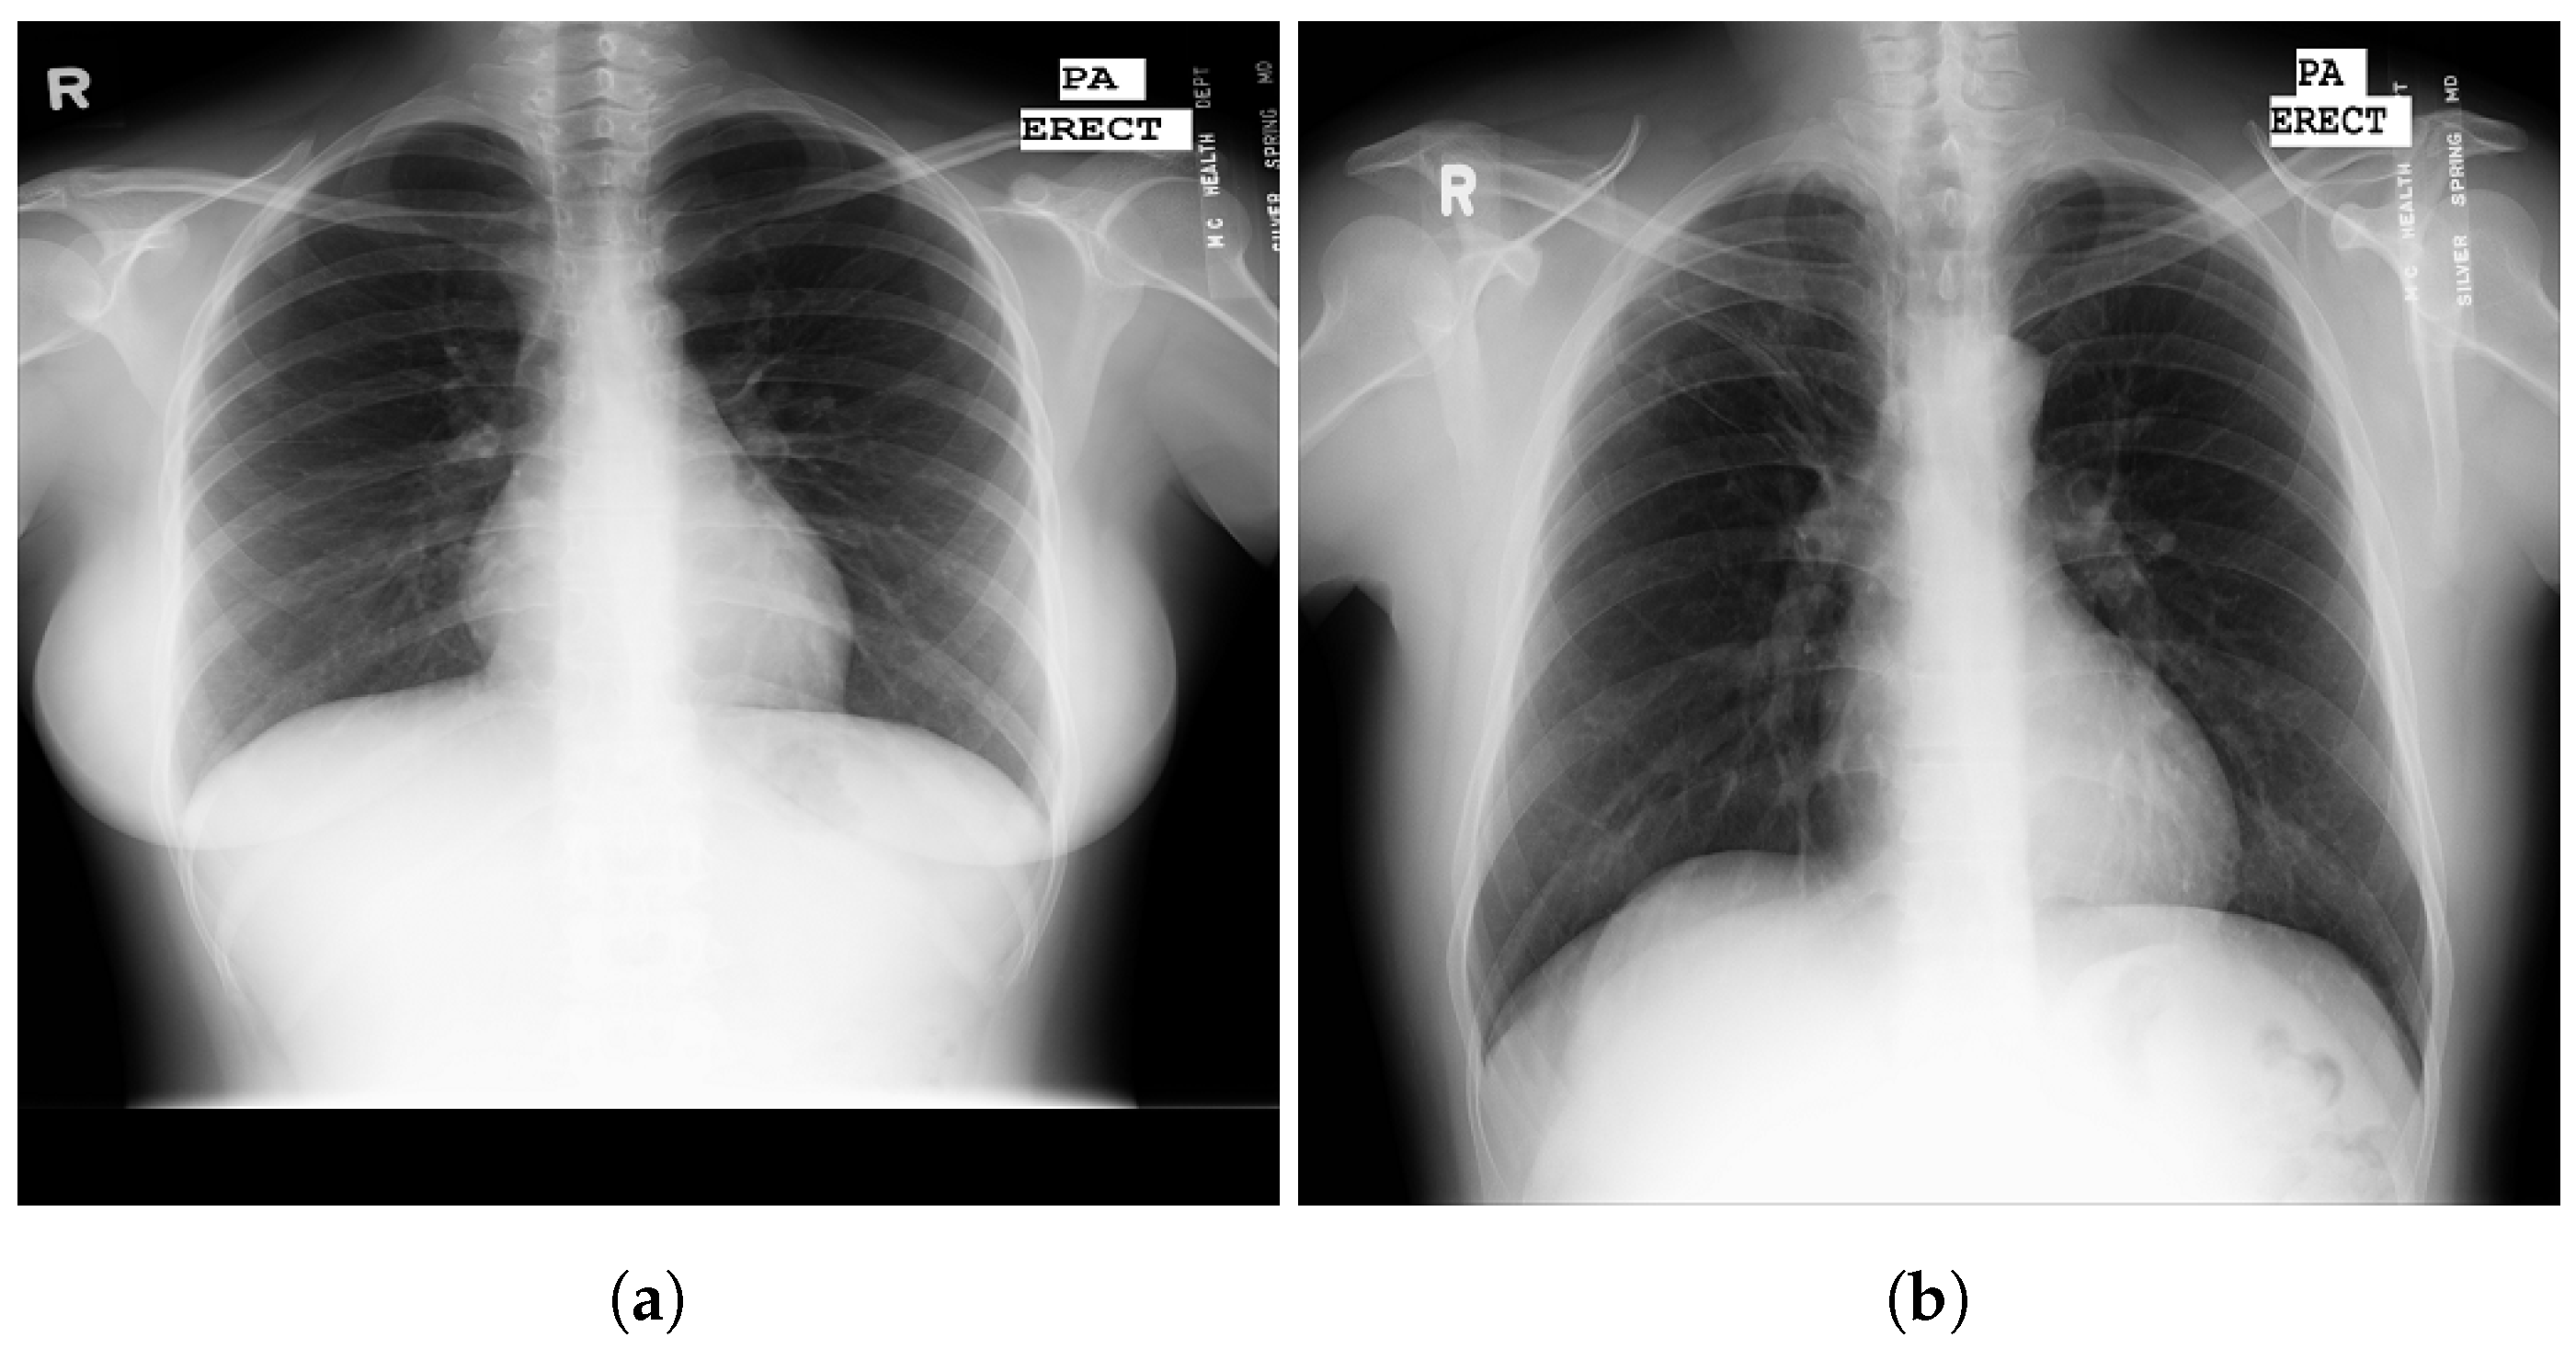

3.5. Chest X-ray Images Pneumonia (CXRIP)

3.6. Montgomery County X-ray